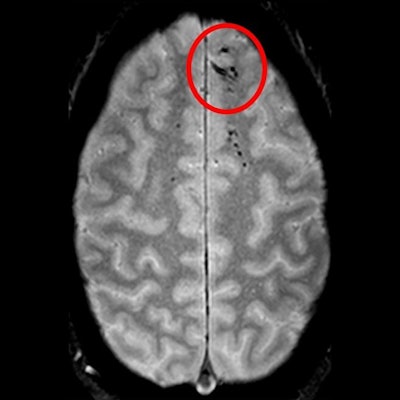

MRI scans of patients with traumatic head injuries have revealed microbleeds that appear as dark lesions and are often too small for detection on CT, according to a study published on October 14 in Brain.

Brain MR images showed evidence of microbleeds in 58% of patients with severe head injury. Most interestingly, 27% of patients with mild cases of head injury also presented with microbleeds on MRI.

The MR images showed the microbleeds as either linear streaks or as dotted lesions, both of which were observed in a majority of patients. The most common location for the microbleeds was in the frontal lobes of the patients, which would indicate head trauma near the forehead. Patients with microbleeds were also more likely to have moderate to severe disability than patients without microbleeds.